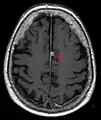

T1 (note CSF is dark) with contrast (arrow pointing to meningioma of the falx)